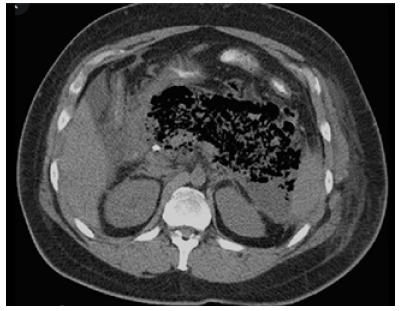

1) Infection of collections - 33% of patients with necrotizing pancreatitis (Figure 2).

2) Hemorrhage - 5% of patients with necrotizing pancreatitis. It can be provoked by inflammatory damage to peripancreatic vessels leading to pseudoaneurysm formation with possible rupture, leading to hemorrhagic shock and death without treatment.

3) Main pancreatic duct disruption - 30% of patients with necrotizing pancreatitis.